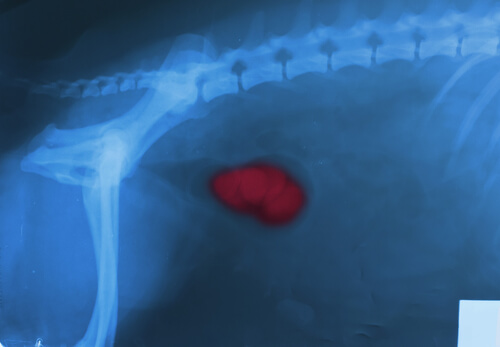

Neoplasias

Las neoplasias, tanto benignas como malignas, son crecimientos anormales de masas en algún órgano o tejido. Por ejemplo, la hiperplasia de próstata, el hemangioma o el hemangiosarcoma causan, generalmente, sangrado.